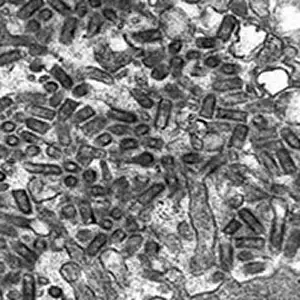

在电子显微镜下,狂犬病毒呈现出一种独特的子弹形状。病毒颗粒长约180纳米,直径约75纳米,一端圆润或呈锥形,另一端则是平坦的基底。这种独特的形态使它成为病毒世界中最容易辨认的成员之一。这种子弹形状并非偶然——它反映了狂犬病毒作为弹状病毒科成员的独特构造。

这张电子显微镜照片展示了一只狂犬狐狸唾液腺中的病毒颗粒。唾液腺腔隙中充满了子弹状的病毒颗粒,它们将随着唾液被注射到下一个受害者体内。这是狂犬病毒传播链中最关键的一环。